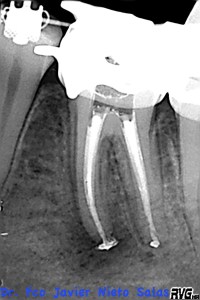

Le realizamos el tratamieto endodóntico del sistema de conductos en dos sesiones, soy un fiel defensor del medicameento intraconductos por varios motivos que quizás no sea el momento de comentar.

Usamos la técnica de ola continua de calor descrita por Buchanan y el backfilling se hizo con gutapercha inyectada.